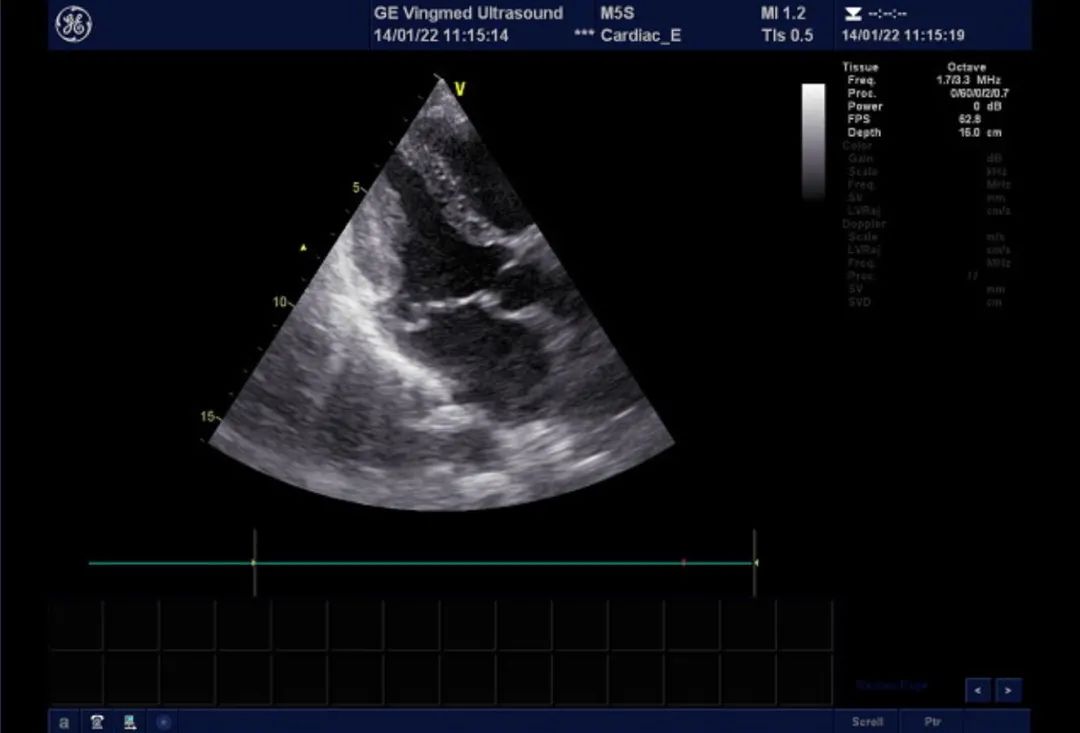

二尖瓣后叶脱垂,大量返流

双孔型房缺,分别为1cm及8mm大

术中食道超声提示二尖瓣瓣叶冗长,组织增厚,多处返流。提示barlow综合征可能。

术中食道超声监测